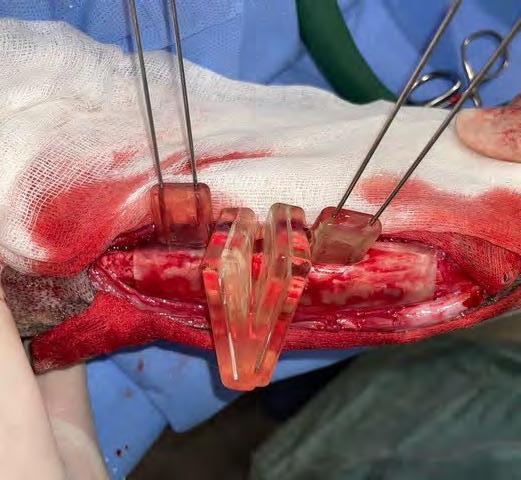

Tras exponer el radio, el primer paso consistió en posicionar la guía de corte en la zona cráneo/medial del área media/distal de este hueso (según lo planificado), fijando temporalmente su posición con la ayuda de 4 agujas introducidas a través de los orificios proximales y distales de la guía. Una vez fijada, se realizaron los cortes con una sierra oscilante recta a través de las dos ranuras del dispositivo (Fig. 3B). A continuación, en un segundo paso, se retiró la guía de corte y se sustituyó por la de alineación, empleando el mismo sistema de fijación con agujas para conseguir la reducción de los fragmentos, según la planificación prevista. Esta segunda guía está diseñada para poder mantener en la posición adecuada los fragmentos mientras se estabilizan con la placa principal (Fig. 4A).

Figura 3. (A) Reproducción en 3D de la aplicación de la guía quirúrgica que permitirá realizar los cortes adecuados sobre el cúbito y radio (ostectomía) posibilitando así la mejor alineación de estos huesos. (B). Imagen de la colocación de la guía quirúrgica durante la intervención.

Figura 4. (A) Reproducción en 3D de la aplicación de la guía de alineación para mantener la fijación de los huesos mientras se coloca la placa principal.

(B) Aspecto de la placa puente recién colocada junto a la guía de alineación.